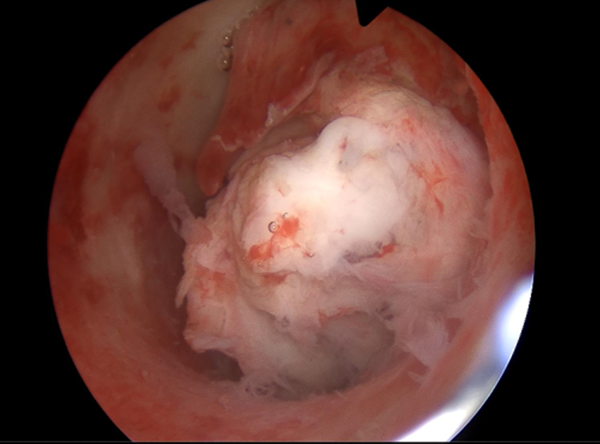

手术时,通过宫腔镜,我们清楚地看到了那个“罪魁祸首”——它圆滚滚的,像个饱满的山竹,正好堵在宫腔里。

手术很顺利,我们把肌瘤完整取了出来。才过了3个小时,李女士就能自己下床走路、吃饭了。她特别惊讶:“我以为肯定要开一刀,没想到这么轻松!”